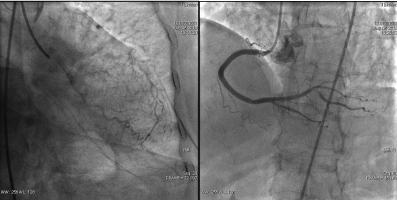

第二次手术过程

手术时间: 2014年8月。

造影结果: LAD病变较前未见明显变化,RCA次全闭塞,LCX支架内100%闭塞。

![]()

手术过程: 再次支架植入,效果良好恢复血流,TIMI3级。